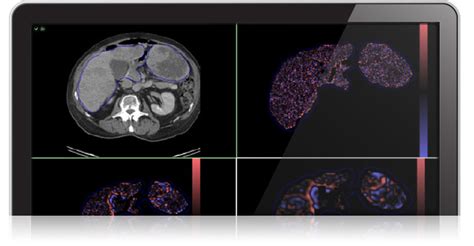

Alright, let’s kick things off with a look at the advanced imaging techniques that are at the forefront of this revolution. We’re not just talking about your run-of-the-mill X-rays anymore, guys. We’re dealing with sophisticated technologies that offer incredible detail and precision. Magnetic Resonance Imaging (MRI) is a game-changer, providing high-resolution images of soft tissues, which makes it ideal for visualizing the brain, spinal cord, and internal organs. The images can be used to assess tumor size, response to treatment, and detect other abnormalities. Then there’s Computed Tomography (CT) scans, which use X-rays to create cross-sectional images of the body. They’re super useful for quickly identifying issues like bone fractures, internal bleeding, and tumors. But, the real magic happens when we combine these techniques with advanced imaging modalities.

One such technique is Positron Emission Tomography (PET) scans, which use radioactive tracers to visualize metabolic activity in the body. This is particularly useful for detecting cancer, as cancer cells often have a higher metabolic rate than normal cells. You can see the difference really clearly! The images allow doctors to see the cancer’s spread. Moreover, we have functional MRI (fMRI), a specialized MRI technique that measures brain activity by detecting changes in blood flow. This is crucial for understanding how the brain functions and for diagnosing neurological disorders. The latest advancements include the use of artificial intelligence (AI) and machine learning (ML) in image analysis. AI algorithms can be trained to automatically detect and quantify features from medical images, significantly speeding up the analysis process and improving accuracy. They also provide quantitative measurements, leading to more objective and reproducible results, which are vital for clinical trials and patient monitoring. The integration of advanced imaging techniques is transforming the way we see diseases and will continue to be a driving force in medical imaging.